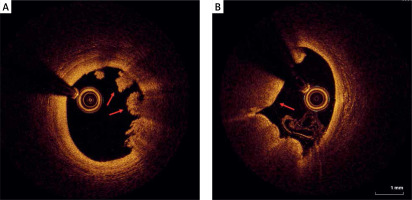

Plaque rupture

As mentioned before, the plaque rupture might be the potential coronary artery lesion responsible for MINOCA, as well as the most frequent mechanism of coronary thrombosis [14]. It can be identified by OCT as a fibroatheroma with fibrous cap disruption over the necrotic core, with or without cavity formation (Figure 2) [18]. When the necrotic core comes into contact with the bloodstream, the thrombus is formed. A typical sign of plaque rupture is the presence of flaps, which are left over from a tear of a fibrous cap that protrudes into the vessel lumen. In OCT, flaps appear bright and relatively homogeneous. The rupture creates a connection between the vessel lumen and the plaque lumen, which often remains empty, diffusely delineated, and appears dark.